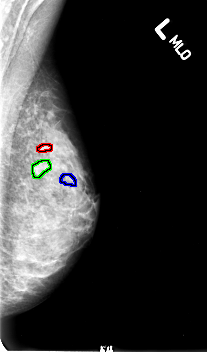

FILE: B_3005_1.LEFT_MLO.OVERLAY

TOTAL_ABNORMALITIES 3

ABNORMALITY 1

LESION_TYPE CALCIFICATION TYPE PUNCTATE-AMORPHOUS-PLEOMORPHIC DISTRIBUTION CLUSTERED

ASSESSMENT 4

SUBTLETY 3

PATHOLOGY MALIGNANT

TOTAL_OUTLINES 1

BOUNDARY

ABNORMALITY 2

ABNORMALITY 3